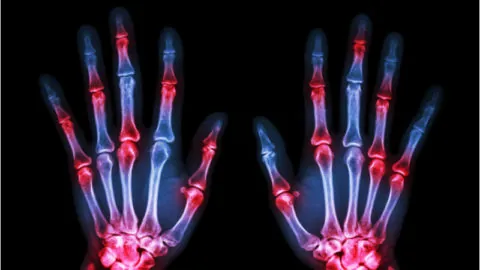

A study published in Aging has found that osteopontin's effects on bone remodeling may be at least partially responsible for osteoarthritis. What is osteopontin? Osteopontin is a glycoprotein found in the extracellular matrix of bone tissue. This is a cytokine that is used in intercellular communication, and it promotes both the proliferation [1] and apoptosis...